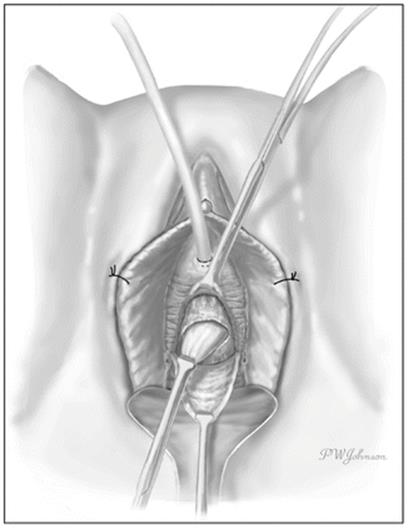

The Foley catheter is usually seen following complete excision of UD (Fig. 11.9). The urethra can be reconstructed over as small as a 12F Foley catheter without long term risk of urethral stricture [1] and should be closed in a watertight fashion with running or interrupted 4.0 synthetic absorbable suture. The closure should be tension-free and water tight (Fig. 11.10). In rare circumstances, a UD may extend circumferentially around the urethra and require segmental resection of the involved portion of the urethra and complex reconstruction [3, 65].

Fig. 11.9

The urethral catheter is seen after complete excision of the UD sac (Used with permission from Rovner ES. Urethral diverticula. In: Female Urology, 3rd ed. Edited by Raz S, Rodriguez LV. Philadelphia: Saunders Elsevier; 2008)